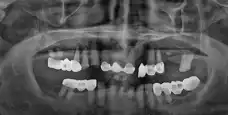

전

임플란트 첨이라서 무서웠는데 치과 여러군데 다녀봤는데 다른데는 무조건 뽑아야된다고 하는데 여기는 왜 뽑아야되는지, 빼고나선 어떤 치료 진행되는지까지 이해하기 쉽게 설명해주시네요 엄청 친절하게 설명해주시니 마음이 놓였어요 상담 선생님들 친절하고 잘해주시고 여기가 최고네요 병원도 엄청 크고 시설도 좋고 깨끗하고 체계도 잘 잡혀있는 것 같어요 감사합니다~